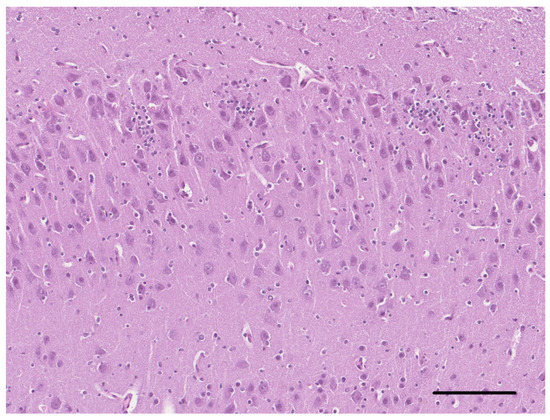

Three cases of the malformation of the cortical development are described: a mixed breed dog and a Border Collie pup with a focal and diffuse cortical dysplasia, respectively, and a kitten with lissencephaly. All cases presented with intractable epilepsy and were euthanized, due [...] Read more.

Three cases of the malformation of the cortical development are described: a mixed breed dog and a Border Collie pup with a focal and diffuse cortical dysplasia, respectively, and a kitten with lissencephaly. All cases presented with intractable epilepsy and were euthanized, due to the cluster of epileptic seizures. The gross examination at necropsy revealed the morphologic alteration of the telencephalic region in two cases. Histopathologically, a disorganization of the cortical lamination with the presence of megalic neurons, was found in the focal cortical dysplasia case. An altered organization of the white and gray matter, with a loss of the normal neuronal distribution and altered neurons, characterized the diffuse cortical dysplasia case. In the lissencephalic cat, there was no recognizable organization of the brain with areas of neuroglial tissue forming nodules in the leptomeningeal space. We strongly support the hypothesis that, as in humans, as well as in the veterinary patients, malformations of the cortical development could be the cause of refractory epilepsy. Full article